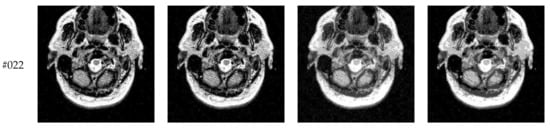

This subsection compares segmentation results of different algorithms (Proposed, Otsu, IIMT, and HL-IIMT) on images containing noise. Figure 13 displays five images with Gaussian noise N (0, 0.001) added to images #022, #042, #062, #082, and #102, which were selected from Figure 9.

Figure 14 displays the segmentation results of images containing noise with a single level of thresholding K = 1. It can be observed that segmentation results achieved by HL-IIMT and Proposed are distinctly better than those of Otsu and IIMT, which have many isolated points. Figure 15 depicts segmentation results obtained by different algorithms with multilevel thresholding K = 4. Obviously, segmentation results of Otsu, IIMT, and HL-IIMT are seriously affected by noise, and most regions are blurred. However, the results of Proposed are better, and they have less noise and clearer edges.

Figure 14.

Segmentation results obtained by different segmentation algorithms for images containing noise (K = 1): (a) Otsu, (b) IIMT, (c) HL-IIMT, (d) Proposed.

Figure 15.

Segmentation results obtained by different segmentation algorithms for images containing noise (K = 4): (a) Otsu, (b) IIMT, (c) HL-IIMT, (d) Proposed.

A comparison of the evaluation results for different segmentation algorithms on images containing noise with K = 1, 4 is shown in Table 3, and corresponding comparison charts are given in Figure 16. In Table 3, the best results are marked in bold. It can be noted that Proposed consistently has the highest U values. For images containing noise, both the IIMT-based algorithms (HL-IIMT and Proposed) are superior to the original Otsu method in single threshold segmentation; furthermore, Proposed can achieve satisfactory results in multilevel threshold segmentation compared to the other three algorithms (IIMT, HL-IIMT, and Otsu).